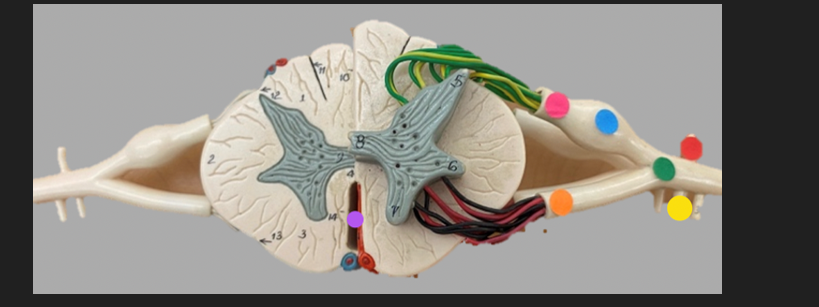

green dot

spinal nerve

orange dot

ventral root

pink dot

dorsal root

blue dot

dorsal root ganglion

red dot

dorsal ramus

yellow dot

ventral ramus

purple dot

anterior median fissure

red dot

posterior (dorsal) horn

purple dot

lateral horn

dark blue dot

anterior (ventral) horn

orange dot

dorsal column

yellow dot

lateral column

dark green

anterior column

line green and pink doit

gray commissure

light blue dot

posterior median sulcus